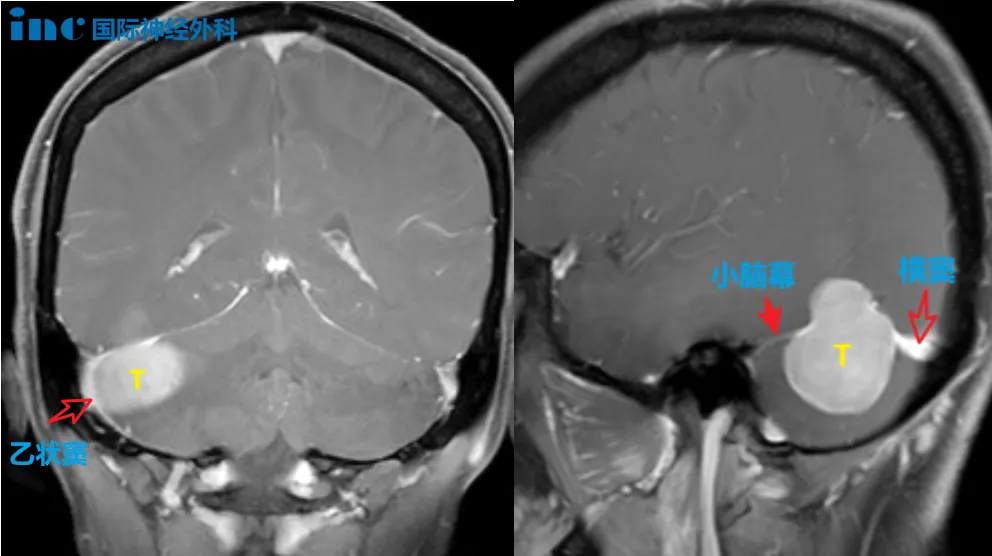

病灶与脑膜呈宽基底且向幕上凸起,边界清晰,右侧小脑半球受压。

▼肿瘤位置与乙状窦、横窦关系密切

由于其体大与周围组织包括神经、血管或者四脑室底黏连重,且后颅窝空间狭小,而肿瘤质地又较硬韧,手术持续时间较长,这些都会对术者的围手术期处理策略、手术技术、以及体力(耐力和毅力)是一个挑战。